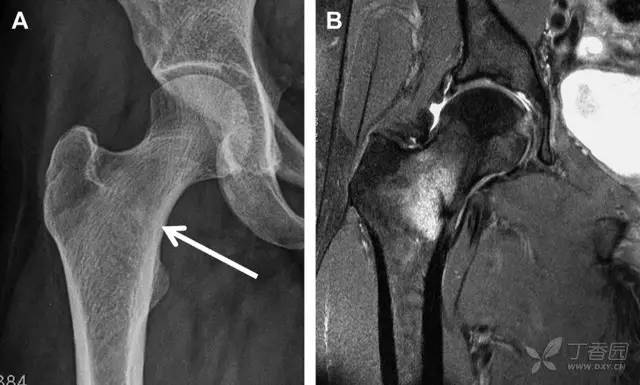

股骨颈应力性骨折在参加耐力运动的运动员中常见,且常发生在股骨颈压力侧。股骨颈基底部发现一垂直于骨皮质的线性硬化带可诊断这种类型的疲劳性骨折(图 8)。

图 8 长跑运动员股骨颈应力性骨折。X 片(A)和冠状位 CT 多维重建(B)图像示穿过股骨颈内侧皮质中的透亮区(箭头),周围硬化。骨折垂直于皮质

股骨颈张力侧的应力性骨折有可能发展为完全骨折(图 9)。

图 9 进食障碍患者股骨颈应力性骨折的张力侧。A 正位片示股骨颈完全骨折。B 2 周前的 X 片示局部骨量减少,正是后来发生骨折的位置(箭头)